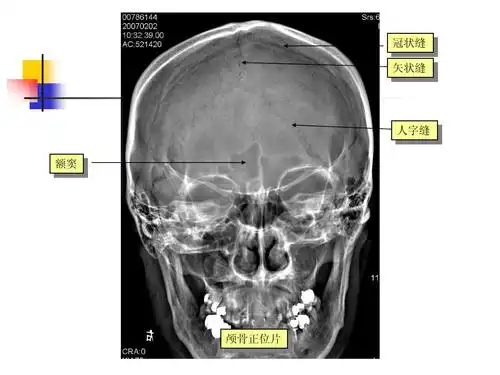

中枢神经系统 医学影像学本科五年制教材(第四版)